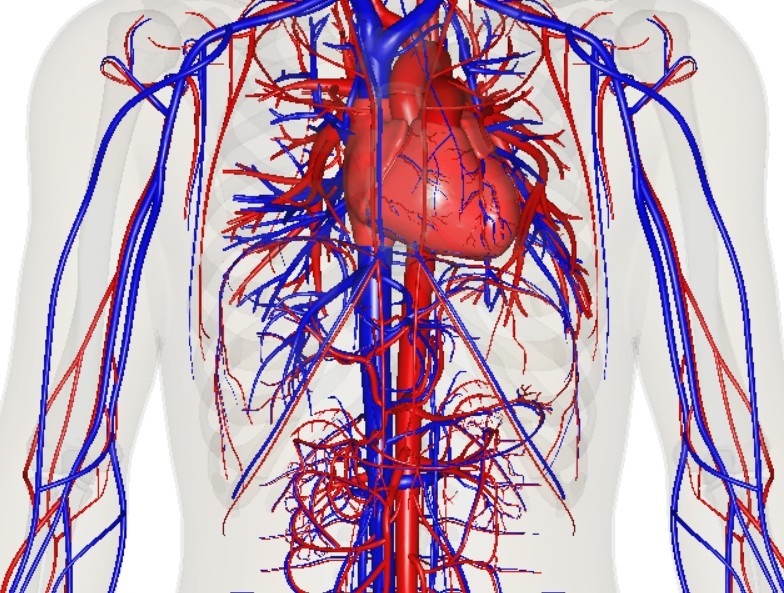

Разработанный препарат, предназначенный для предотвращения разрыва сосудов и обработки патологических образований, обещает быть более эффективным и доступным, чем импортные аналоги. Исследования проводились совместно с хирургами из национального медицинского исследовательского центра имени академика Е. Н. Мешалкина Минздрава РФ.

Полимер, разработанный с использованием электрохимически активных соединений и материалов, успешно прошел тесты на мини-пигах. Его вязкость и светимость были подобраны под различные диаметры сосудов.

В результате исследований ученые создали чистый по составу препарат, лишенный ненужных примесей. Планируется, что в 2024 году начнутся последние этапы разработки, включая упаковку, тестирование на токсичность и клинические испытания. Ожидается, что компания "Медин" уже через год начнет производство отечественных эмболизатов, более доступных по стоимости и чище по составу по сравнению с импортными аналогами, сообщает РИА Новости.